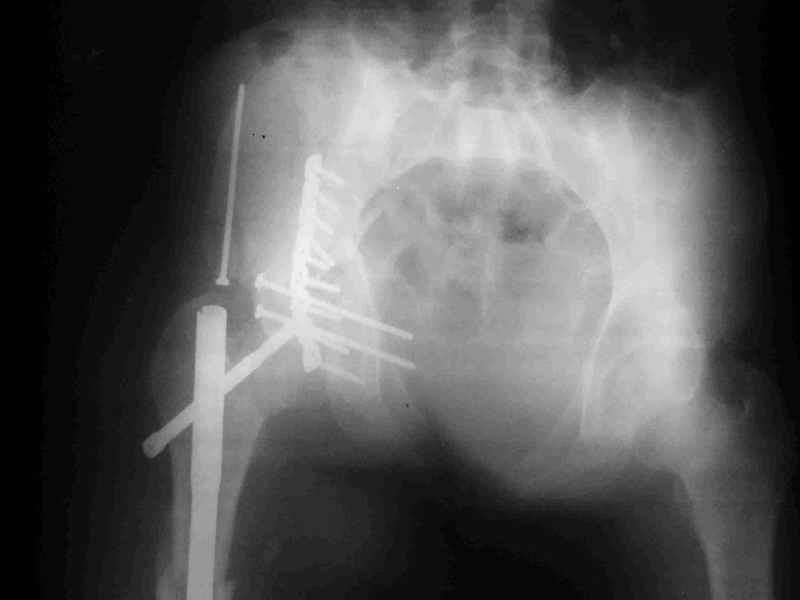

Anatoly F Lazarev 03 Сентябрь 2004, 22:39

Высылаю пример еще одного случая, остеосинтез пластиной из подвздошного доступа.

Анатолий, во второй презентации, какой Ваш диагноз, не поперечный ли перелом ацетабулум? Вы написали, Ваш доступ был подвздошный, по моему мнению, ваш доступ лимитировал Вас к anterior column и постоянно надо было держать в контроле за натяжением femoral artery and vein, иначе грозит закупоркой артерии или вены, (были и такие experience), при сгибании в тазобедренном суставе, которое ухудшает и так ухудшенный доступ. По-моему, если доступ расширить, т.е. formal Ilioinguinal approach то применить пластину подлиннее 12-14 дырок на pelvic brim, через первое окно Ilioinguinal approach, т.е. Symphisis side, после рассечения места прекрепления muscle rectus abdominus, где достаточно места для 4 шурупов, тогда таким образом фиксированный перелом держится более стабильно и 4.5 мм шурупы для колонн можно было бы пропустить через пластину кзади впадины.